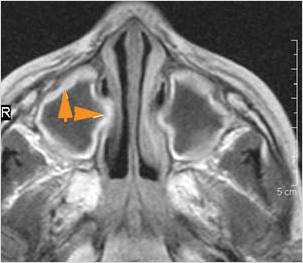

There is evidence of thrombus, thrombophlebitis or other occlusive or inflammatory process of the cavernous sinus. [Yes/No]

There is evidence of inflammation of the distal internal carotid artery. [Yes/No]

The superior and/or inferior ophthalmic veins are dilated or thrombosed. [Yes/No]